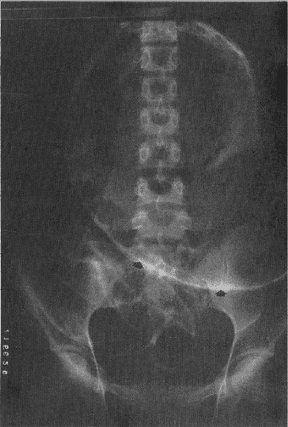

Al examen abdominal se observaba marcada distensión, peristalsis abolida, dolor a la palpación del epigastrio que no permitía la palpación profunda. Se realiza hidratación y colocación de sonda nasogástrica y se practican los siguientes exámenes paraclínicos: Hb: 12.8 g%; Hcto: 38%: Leucocitos 17.800/mm. La radiografía del tórax mostró neumoperitoneo masivo con elevación de los hemidiafragmas, y aire subdiafragmático que desplazaba al hígado hacia abajo y hacía la línea media (Fig. 1). La radiografía simple del abdomen mostró gran dilatación gástrica con traslocación de la curvatura mayor a la derecha, imagen compatible con vólvulo gástrico (Fig. 2). Con estos hallazgos clínicos y paraclínicos se plantea la impresión diagnóstica de abdomen agudo secundario a perforación de víscera hueca, con vólvulo gástrico agudo. Se realiza laparotomía exploratoria por la línea media, encontrándose gran dilatación del estómago que presentaba un vólvulo organoaxial; al destorcerlo se observó una perforación gástrica de aproximadamente 2 cm en la curvatura menor, con laxitud de los ligamentos gastroesplénico y gastrocólico; se realizó reparación de la perforación y gastropexia de la curvatura mayor al diafragma y al peritoneo parietal anterior. La paciente se mantuvo estable durante el acto quirúrgico y la evolución postoperatoria fue satisfactoria; se dio de alta al décimo día postoperatorio.

Fig. 2. Radiografía simple del abdomen que muestra gran dilatación gástrica con transposición de la curvatura mayor a la derecha. |